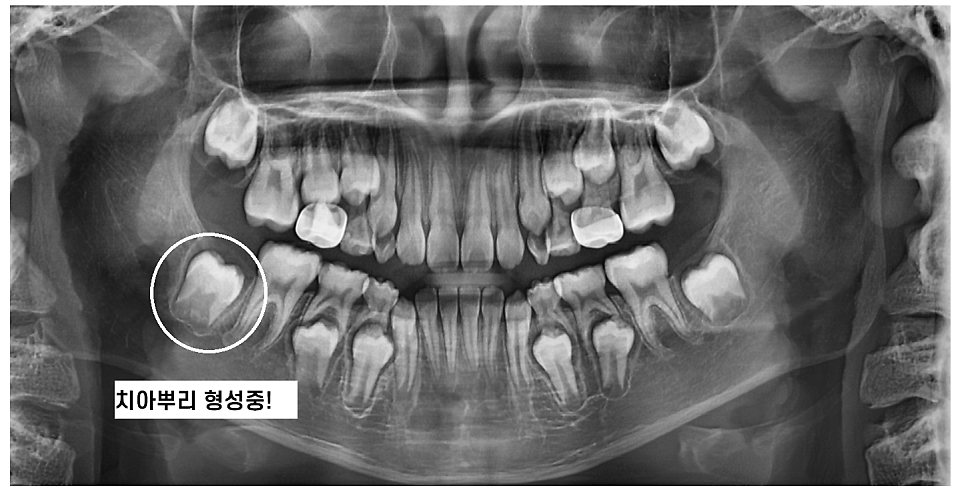

성장기에는 키도 크고 몸도 자라죠~

때문에 성장 중인 어린이나 청소년의 경우

임플란트 치료를 바로 진행할 수 없습니다.

턱 뼈 역시 계속 성장하고 있기 때문이죠!

200207 치아 뿌리도 안만들어졌는데 임플란트를 할 수 없겠죠?

일반적으로 턱뼈의 성장이 끝나는 시기

(여성은 18세 전 후, 남성은 20세 전 후) 치료를 권장하고 있습니다!!